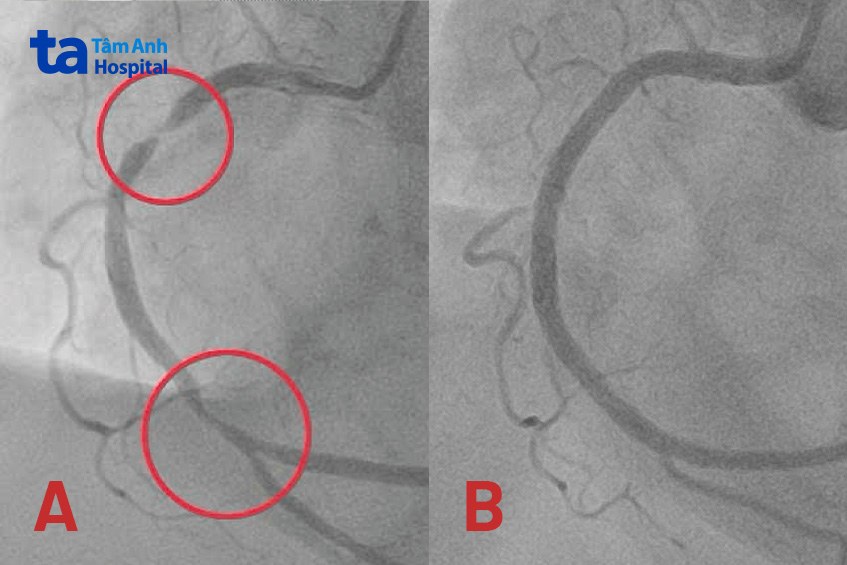

Giáo sư Nhân cùng ê kíp tiến hành chụp và can thiệp động mạch vành cấp cứu cho bà Keelin. Kết quả xác định động mạch vành phải bị hẹp khít đến 99% đoạn giữa và hẹp 80-90% đoạn xa. Các bác sĩ luồn dây dẫn từ động mạch quay (ở cổ tay) đi qua vị trí hẹp nghẽn nặng để nong rộng mạch máu, mở đường cho việc đưa stent vào tái thông mạch vành. Sau gần một giờ, ê kíp đặt thành công 2 stent phủ thuốc tại hai vị trí hẹp nặng, khơi thông con đường đưa máu từ động mạch vành phải đến nuôi tim.